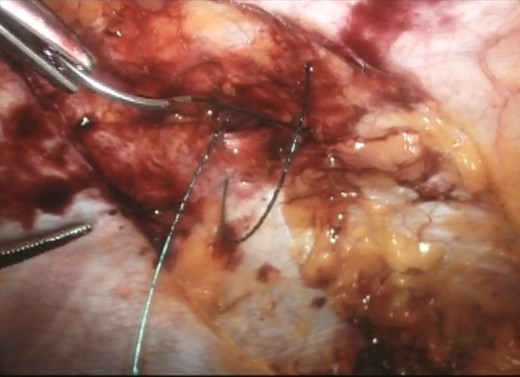

Upon successful reduction (Fig. 4), the hernia neck was closed laparoscopically with an intra-corporeal V-loc™ suture (Fig. 5). Closure of the hernia neck creates muscle apposition thus allowing for effective functioning of the abdominal wall musculature (Fig. 5). We extrapolated this data from incisional herniorrhaphy and the component separation technique [4]. The hernia defect was then covered with an underlay Ventralite™ mesh and secured with Absorbatac™ staples (Fig. 6). The Ventralite™ mesh is a dual layer mesh with one side consisting of an absorbable hydrogel barrier facing the bowel which reduces the risk of bowel adhesions. Her post-operative recovery was uneventful and she was discharged home the same day.

Laparoscopic intra-corporeal suturing of hernia neck with V-loc™ suture.